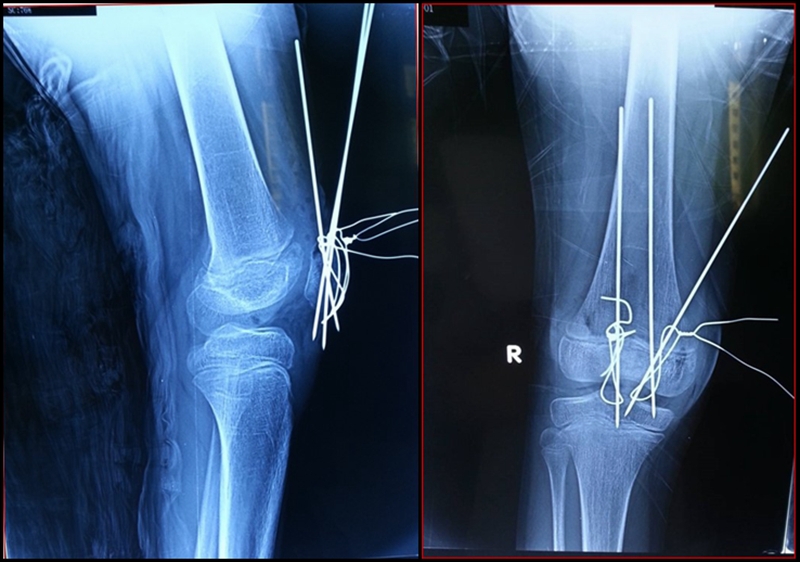

图7 术中X线

图8 术后石膏固定X线

手术关键点在于恢复伸膝装置的连续性,争取解剖复位,并修复髌旁支持带。如果术中因股四头肌腱挛缩出现复位困难,则一期行股四头肌腱延长术。

手术采取腰麻,在止血带下进行。行膝前正中切口,电刀止血。